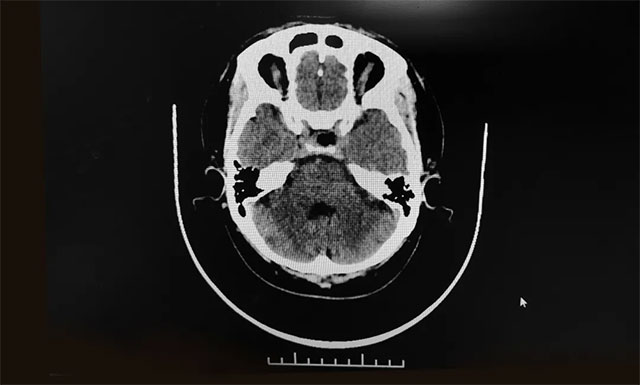

▲ 术后影像显示肿瘤被切除